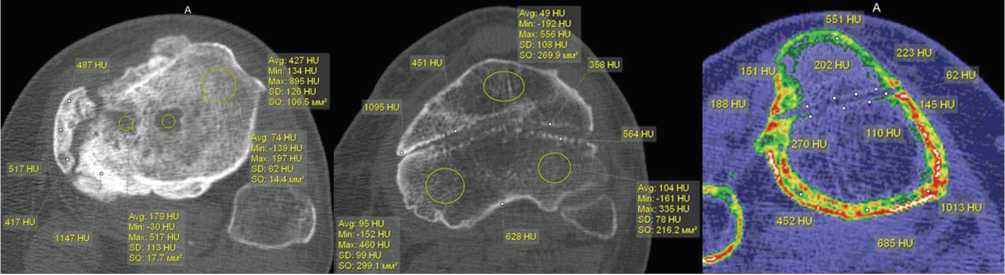

Прогрессирование СО приводило к формированию дефекта кости различной формы и протяженности в области спицевого канала, имеющего четкие контуры со значительным увеличением плотности его стенок. При транскортикальном проведении спицы через проксимальный эпифиз большеберцовой кости плотность фрагмента, расположенного кнаружи от спицевого канала, у 52 % больных была меньше, чем плотность кортикальной пластинки основной части кости. Для каналов от спиц в области проксимального или дистального метафиза или эпифиза большеберцовой кости и дистального метаэпифиза бедренной кости было характерно повышение плотности для стенок канала в виде четкой разграничительной линии с прилежащими участками губчатой кости со снижением ее плотности. Плотность корковой пластинки отличалась в различных отделах на (189,7 ± 96,5) HU. Плотность секвестров в метаэпифизе в 89,5 % случаев была меньше плотности корковой пластинки, — (675,5 ± 93,9) HU (рис. 2).

Рис. 2. МСКТ голени пациента 55 лет со СО, аксиальные срезы

Рис. 3. МСКТ голеней пациентов со СО, аксиальные срезы на уровне проксимального отдела большеберцовой кости

Спицевой канал был шире в области кортикальной пластинки. Плотность стенок спицевого канала увеличивалась до 480 [420;620] HU (медиана) (рис. 4, а). При локализации СО в дистальной трети большеберцовой кости и длительном течении заболевания (больше года) изменения в данной области проявлялись участками деструкции, нарушением структуры кости, появлением зон разрежения и склероза. Во всех случаях воспалительный и деструктивный процесс распространялся на кости стопы, сопровождаясь дефектами, изменением структуры с нарушением органотипического строения костей, зонами резорбции (рис. 4, б, в).

Рис. 4. МСКТ голеней пациентов со СО: а — пациентки 34 лет, MPR в сагиттальной плоскости; б — больного 56 лет, аксиальный срез, массивные периостальные наслоения, ассимилированные с корковой пластинкой; в — MPR этого же больного в сагиттальной плоскости

Увеличение ширины и нечеткие контуры спицевого канала наряду с увеличением плотности его стенок зарегистрированы на ранних стадиях СО. Ширину канала сравнивали с его размерами после удаления спицы у пациентов без воспалительного процесса (контрольная группа). Медиана ширины спицевого канала в области диафиза в этих случаях составляла 1,6 [1,4;1,7]. Ширина спицевого канала после удаления спицы при септическом остеомиелите в области диафиза колебалась в значительных пределах, — от 3,5 мм до 7,0 мм. Медиана ширины спицевого канала в диафизе у пациентов со СО составила 4,1 мм [межквартильный размах 3,8;5,1 мм]. Для сравнения, — в области эпифиза ширина спицевого канала была меньше и составляла 2,6 мм [2,8;3,1 мм], что связано с анатомическими особенностями строения проксимального отдела большеберцовой кости в этой зоне (рис. 5).

Рис. 5. МСКТ голени пациентов 36 лет (а) и 42 лет (б) со СО. Ширина спицевого канала: а — аксиальный срез; б — MPR в сагиттальной плоскости